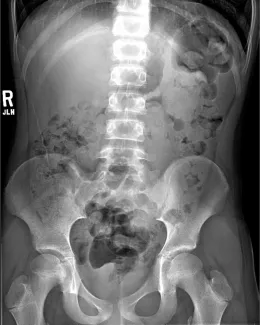

Abdominal Xrays are necessary to evaluate the effectiveness of the laxative or enema therapy and to identify the amount of stool in the colon. These will be done at each office visit.

Firm bowel movements can be painful to pass. This can lead to stool with-holding which further worsens constipation. Blood streaks lining the firm stools may mean anal fissures, which are cracks or tears near the anus caused by passing hard stools. If this is noted, increase fluid intake and call our office to schedule a clinic visit and an abdominal Xray. The dose of oral laxatives may need be increased before the clinic visit.